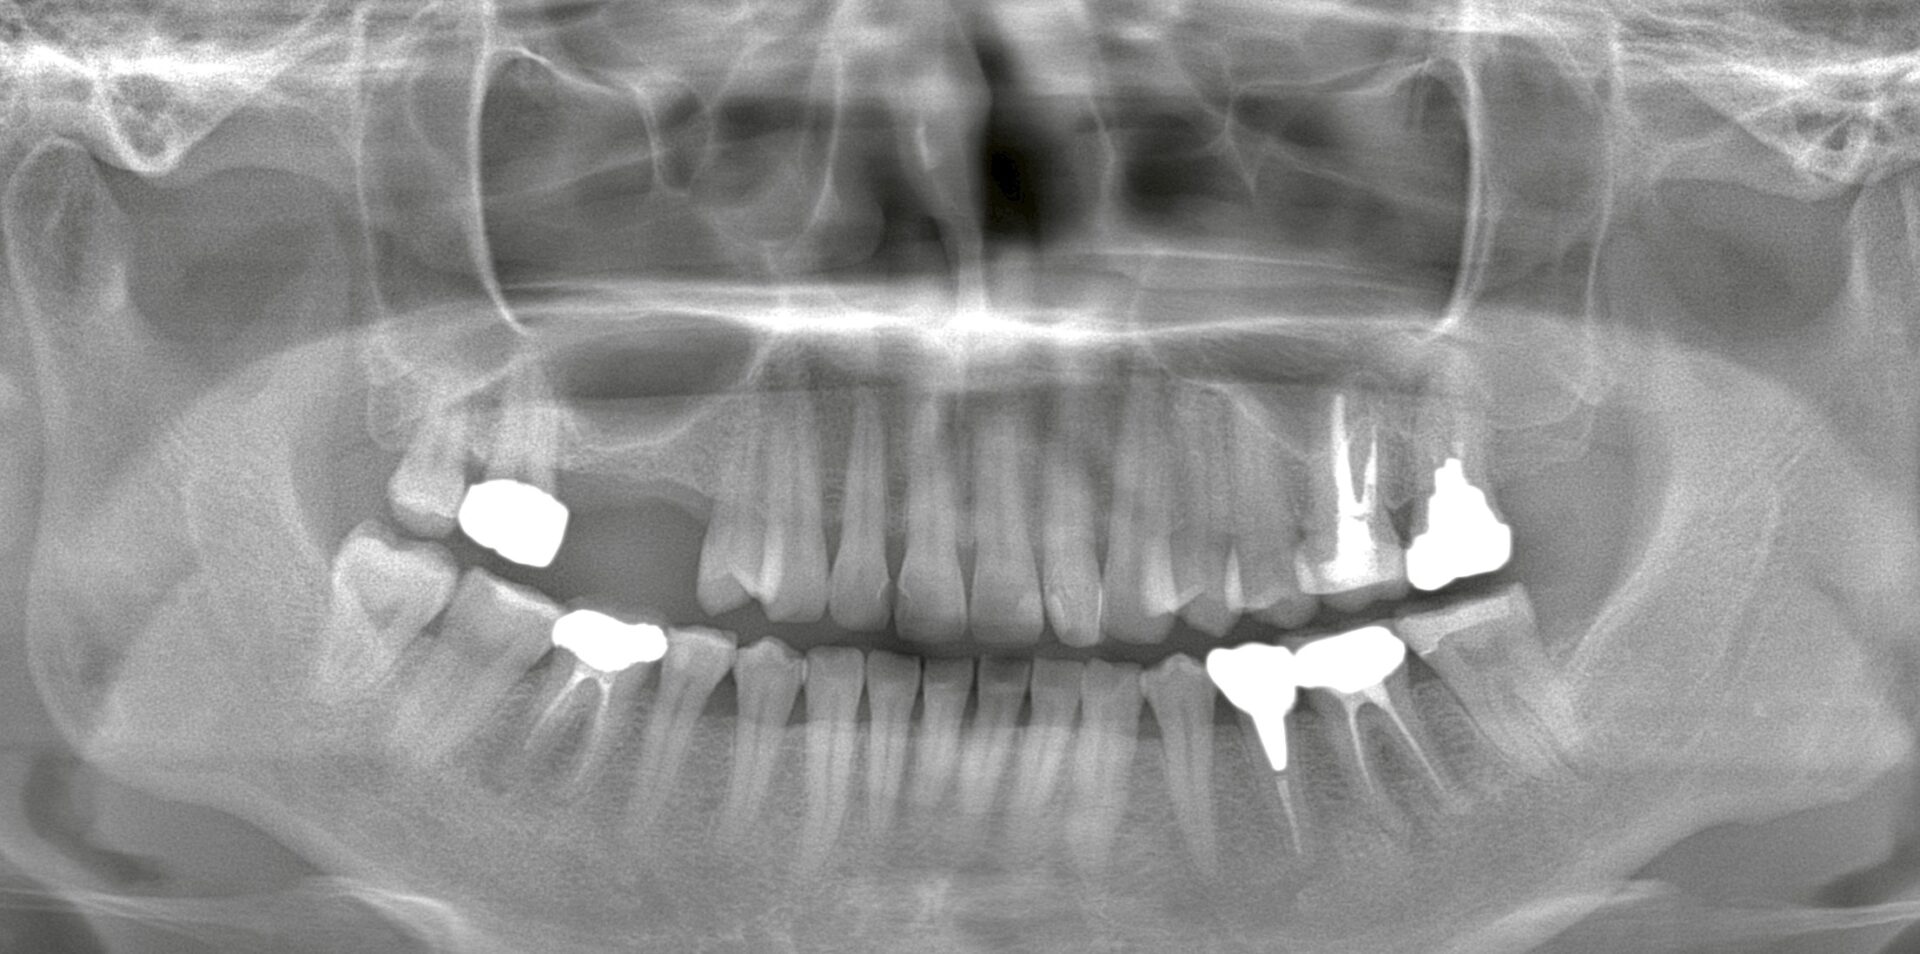

右上の欠損部をパノラマ撮影にて確認したところ、上顎洞との著しい近接が認められました。

このままインプラントを埋入すると、インプラント体が上顎洞内に迷入してしまうリスクがあります。

今回のプランニングでは、既存骨の厚みがわずか2mm弱の部分があり、骨造成(サイナスリフト)を行ってからのインプラント埋入が必要となります。